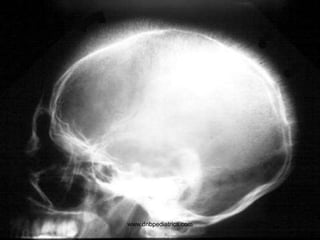

www.dnbpediatrics.com

Questions

• Describe the lesion?

• Give two D/D

• Osteolytic lesion of skull

• Histiocytosis

Metastasis

• Hyperuricemia, hyperkalemia, and

hyperphosphatemia